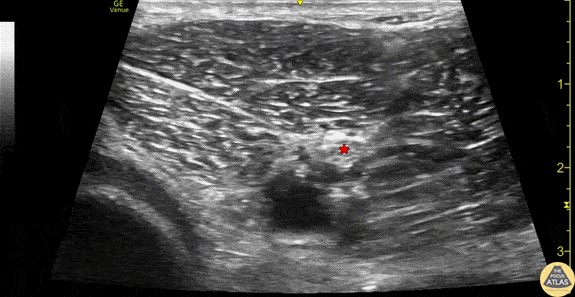

Anatomy of the sciatic nerve in the popliteal fossa. This image was obtained using the linear transducer in a transverse orientation in the popliteal fossa. The sciatic nerve (*) can be seen superficial to the pulsating popliteal artery, just superficial to the partially compressed popliteal vein. The hyperechoic femoral condylar cortex can be seen at the left of the image. Drs. Sam Paskin-Flerlage, PGY4 and Michael Heffler, PGY3 Denver Health Residency in Emergency Medicine